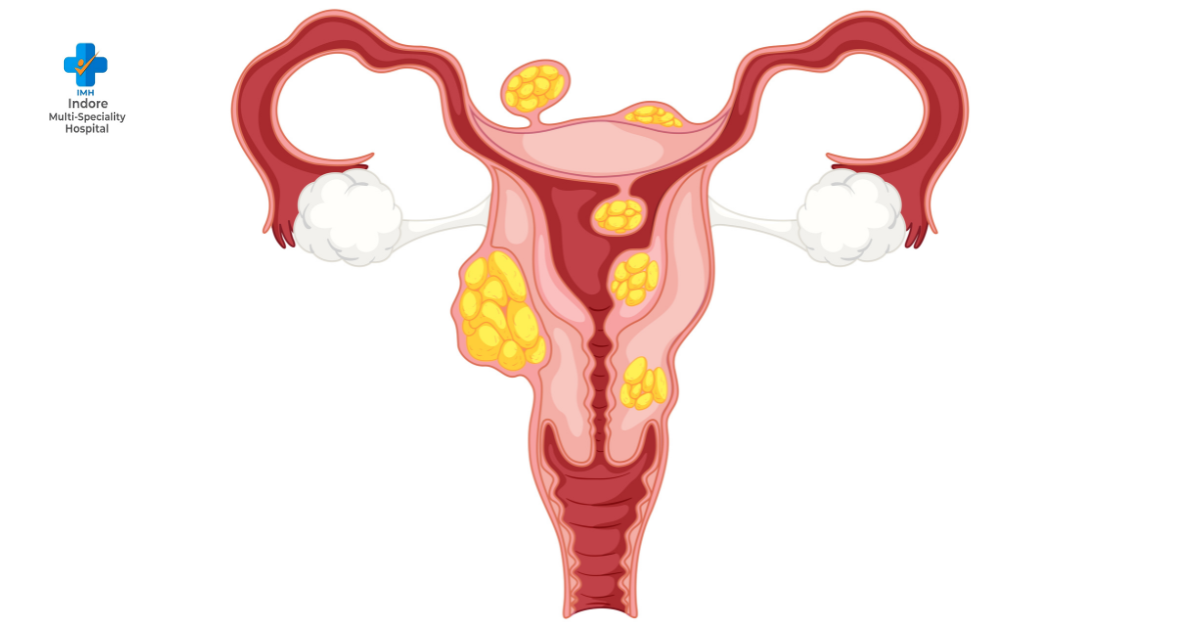

Polycystic Ovary Disease (PCOD) is a common hormonal disorder affecting young women, often leading to irregular periods, weight gain, and other health issues. Seeking PCOD treatment in Indore at a reputed clinic can provide expert guidance and personalized care for women experiencing these challenges. Some early signs to watch for include:Irregular Menstrual Cycles: Missing periods or having cycles that vary widely in length. Consulting a reliable clinic for PCOD treatment in Indore ensures personalized care and access to the latest treatment options. By staying aware of early signs and adopting healthy lifestyle habits, young women can effectively manage PCOD and lead a healthier life.